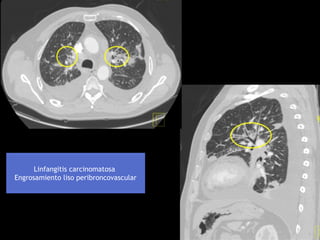

Linfangitis carcinomatosa por carcinoma en pulmón izq.

Engrosamiento liso peribroncovascular

Linfangitis carcinomatosa